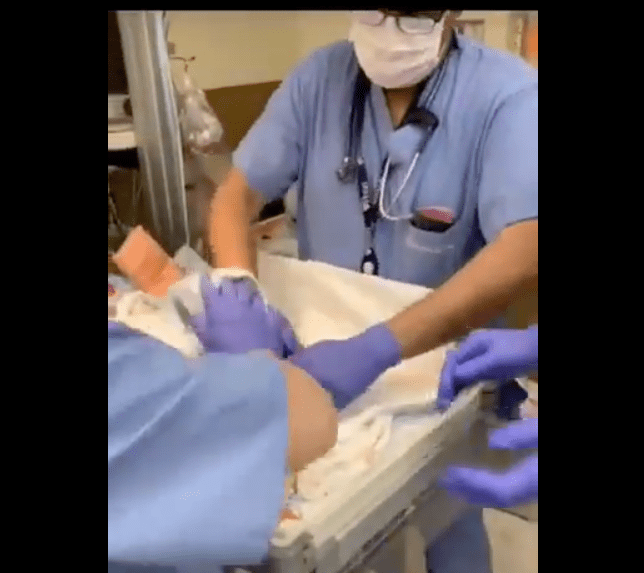

Un video en redes mostró el instante en que un doctor de Arizona dejó caer a un bebé recién nacido que se le resbaló de las manos y golpeó la cabeza sobre una mesa.

De acuerdo con las imágenes, el bebé cayó de cabeza al momento de nacer, después de que se resbalara de las manos del equipo médico en el Centro Médico Chandler Regional, en Arizona, en febrero; el bebé, que nació prematuro, sufrió una hemorragia cerebral días después del incidente, informaron los padres.

La grabación fue hecha por el padre del bebé, mostrando cómo el médico toma al menor con una sola mano y luego se le resbala y golpea la cabeza contra una mesa, y casi cae de la mesa donde golpeó, explicó el padre. Monique y Derrick Rogers, los padres de la criatura, amenazan con tomar acciones legales porque, señalan, que el equipo médico nunca les explicó por qué la recién nacida tuvo hemorragia cerebral días más tarde.